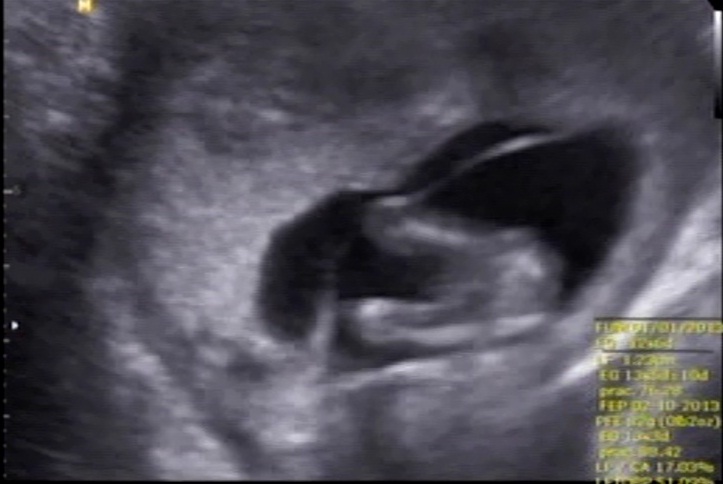

Boy or girl? 14 weeks.

Would you guess boy or girl? Could the white in the first pic be boy parts?

They are from a 14 week scan. Im having an other scan soon but im soo curios and would like to know what to expect when I go to that scan.

It seems to have something between the legs. My guess is a boy, hope this is what you want

Looks like there is something between the legs I would say boy.